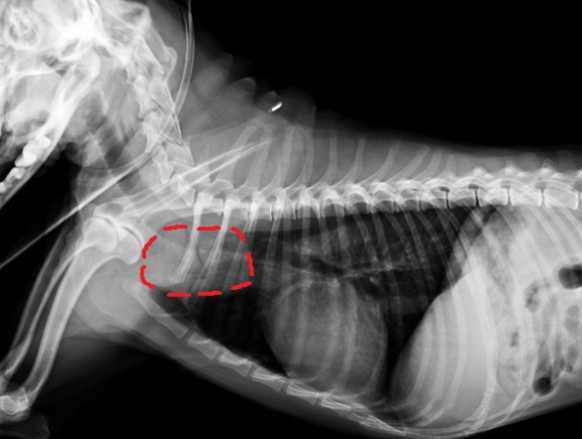

診斷流程:一步步揭開真相

獸醫通常會結合多種工具來確認狗狗胸腔腫瘤,流程大致如下:

| 診斷方法 | 優點 | 限制 | 適用情況 |

|---|---|---|---|

| X光檢查 | 快速、便宜,能看腫瘤大致位置 | 無法區分腫瘤類型或細部結構 | 初步篩檢的首選 |

| 超音波 | 可評估腫瘤血流和周圍組織 | 受氣體干擾,肺深部看不清楚 | 配合X光用於心周邊腫瘤 |

| CT掃描 | 3D影像,精準定位腫瘤大小 | 費用較高,需麻醉 | 手術前評估或複雜案例 |

| 活組織檢查 | 確診腫瘤類型的黃金標準 | 侵入性,有微小風險 | 需制定治療方案時必做 |

行政院農業委員會的動物保護資訊網提到,活檢雖然聽起來可怕,但現在有細針抽吸等微創技術,風險已降低很多。阿福做活檢時我只緊張了半小時,結果出來反而安心,因為終於能對症下藥。

為什麼診斷要分階段?

很多家長會問:「不能直接做CT嗎?」其實分階段是為了避免過度檢查。X光先抓大致方向,有必要再進階,省錢也減少狗狗壓力。獸醫通常會根據狗狗年齡、品種和症狀決定順序。